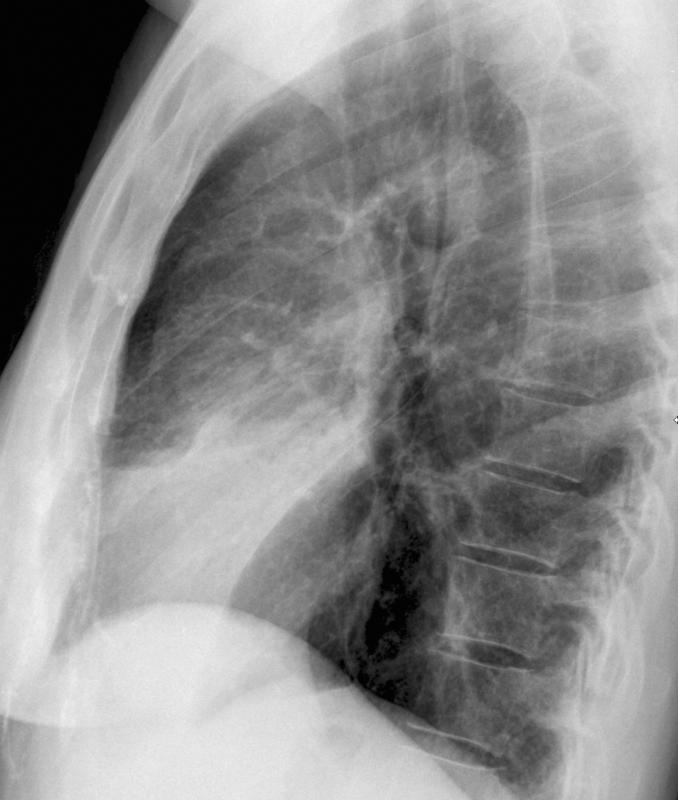

Pneumonia

Lingular pneumonia Lat

Date: 10/15/2006